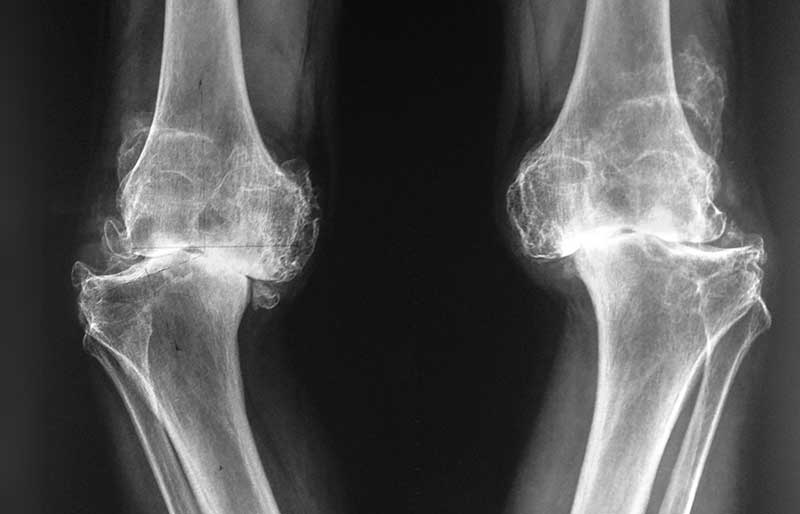

Operasi penggantian sendi lutut adalah suatu operasi untuk mengganti sendi lutut yang rusak akibat osteoartritis (penipisan tulang rawan) dengan sendi buatan yang disebut prosthesis. Penyebab utama kerusakan sendi lutut adalah osteoartritis (baca pen- jelasan tentang “Osteoartritis”) dan sendi yang paling sering terserang osteoartritis adalah lutut.

Operasi penggantian sendi lutut merupakan pengobatan terbaik untuk osteoartritis lutut stadium 3 dan 4. Ada empat tujuan operasi ini, yaitu menghilangkan rasa sakit sendi yang telah rusak, memperbaiki lingkup gerak sendi yang sebelumnya kaku dan terbatas, mengembalikan kemampuan penderita melakukan aktivitas harian tanpa rasa sakit, dan meningkatkan kualitas hidup sehingga penderita kerusakkan sendi dapat menjalani hidup secara aktif bebas dari nyeri sendi.